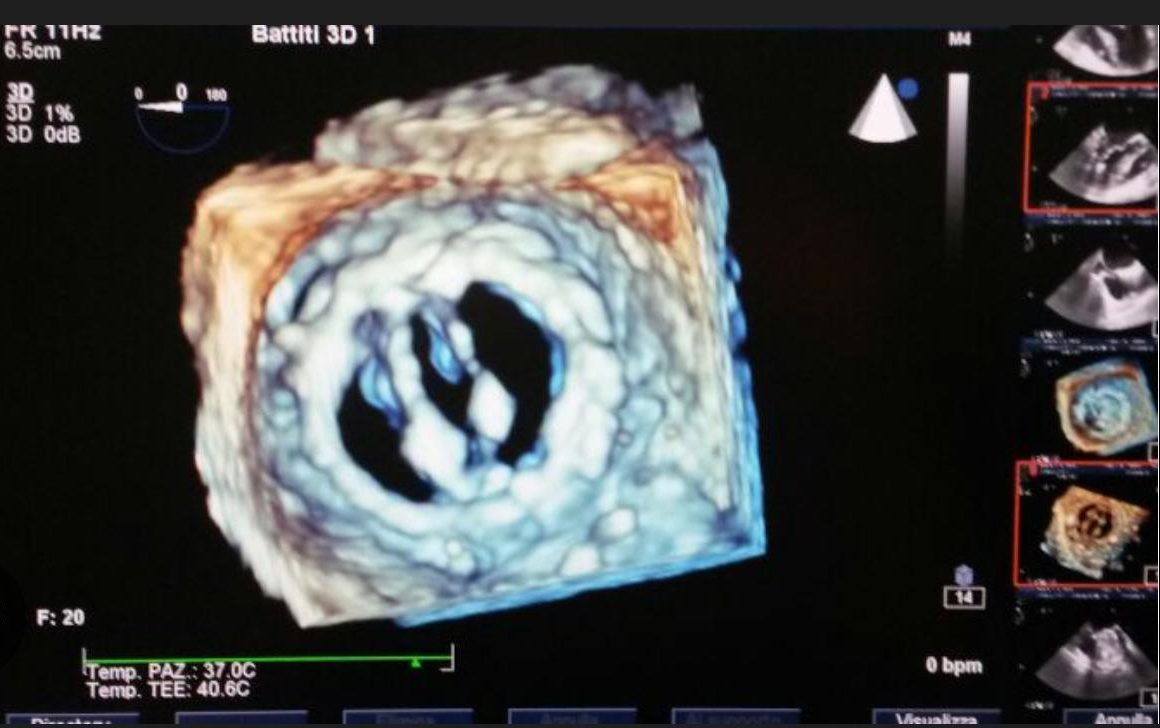

Ecocardiogramma tridimensionale

L’ecocardiogramma tridimensionale (3D) è un esame diagnostico che utilizza gli ultrasuoni per ottenere immagini tridimensionali del cuore in tempo reale.

Consente di visualizzare con maggiore precisione le camere cardiache, le valvole, il movimento delle pareti e la funzione di pompa del cuore.

È particolarmente utile per valutare malformazioni cardiache, patologie valvolari e per la pianificazione di interventi cardiologici.